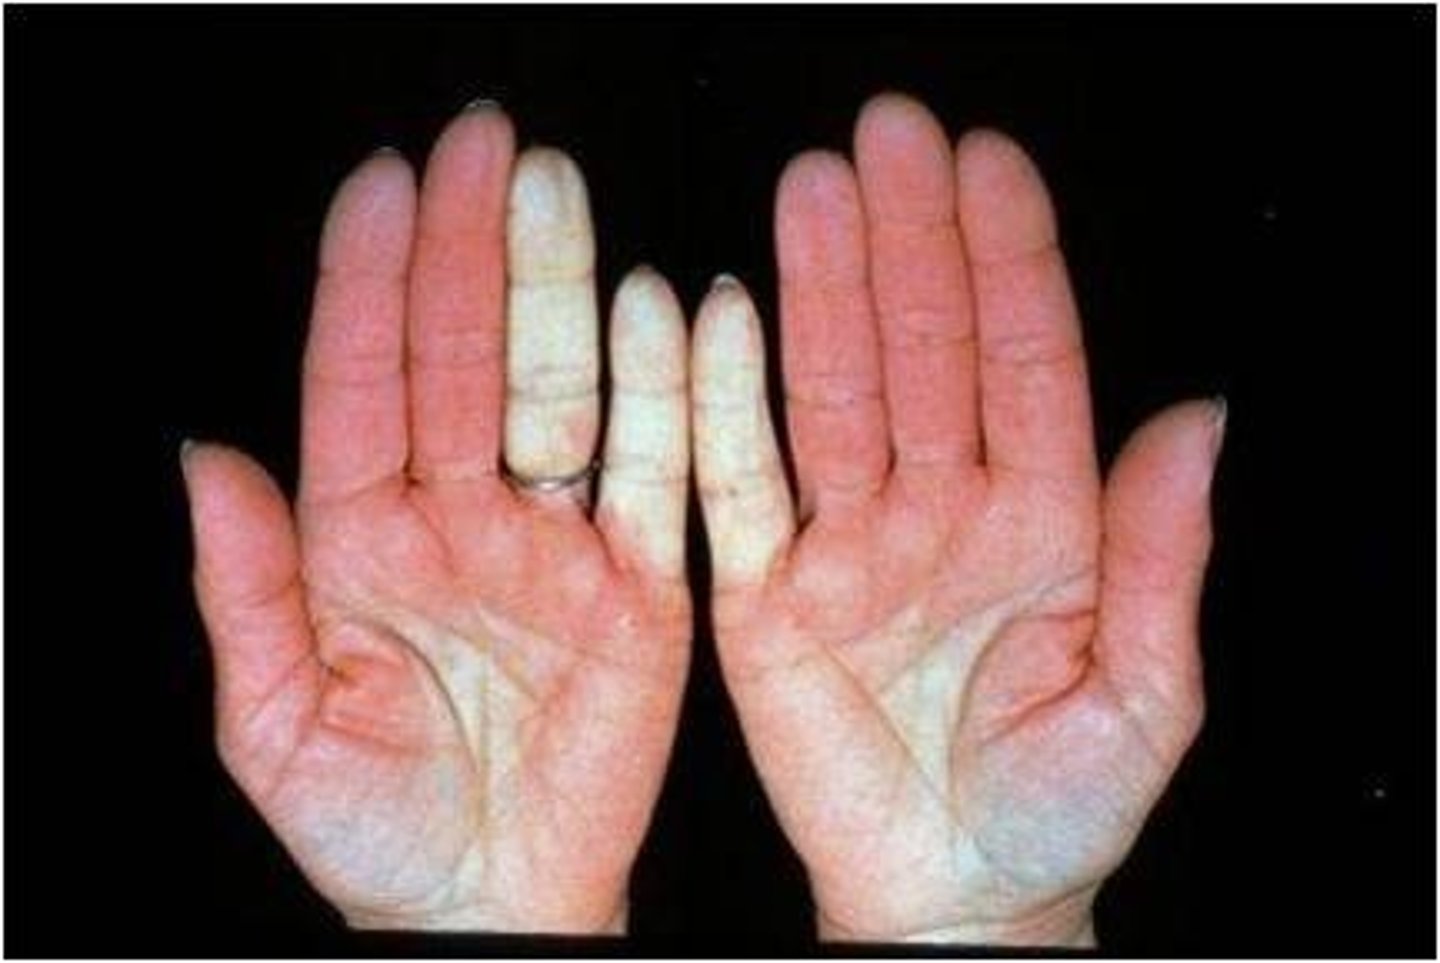

Painful fingers/toes changing color from blue to white to red with cold or stress

Raynaud phenomenon (vasospasm in extremities)